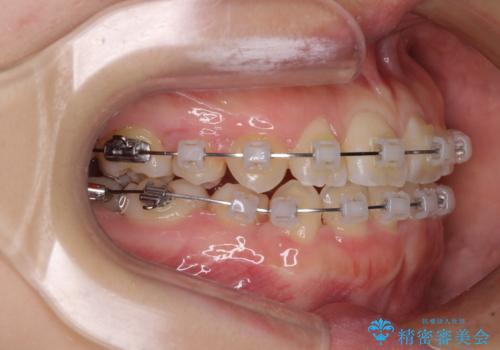

- クリアブラケット

- 2年3ヶ月

親知らずの抜歯により埋もれた奥歯周辺の歯肉が切除され、矯正装置が装着できるようになりました。

奥歯の移動、特に下顎大臼歯の移動は時間がかかることが多く、3年以上の治療期間を想定していましたが、想像以上に動きがよく、2年強で終えることができました。